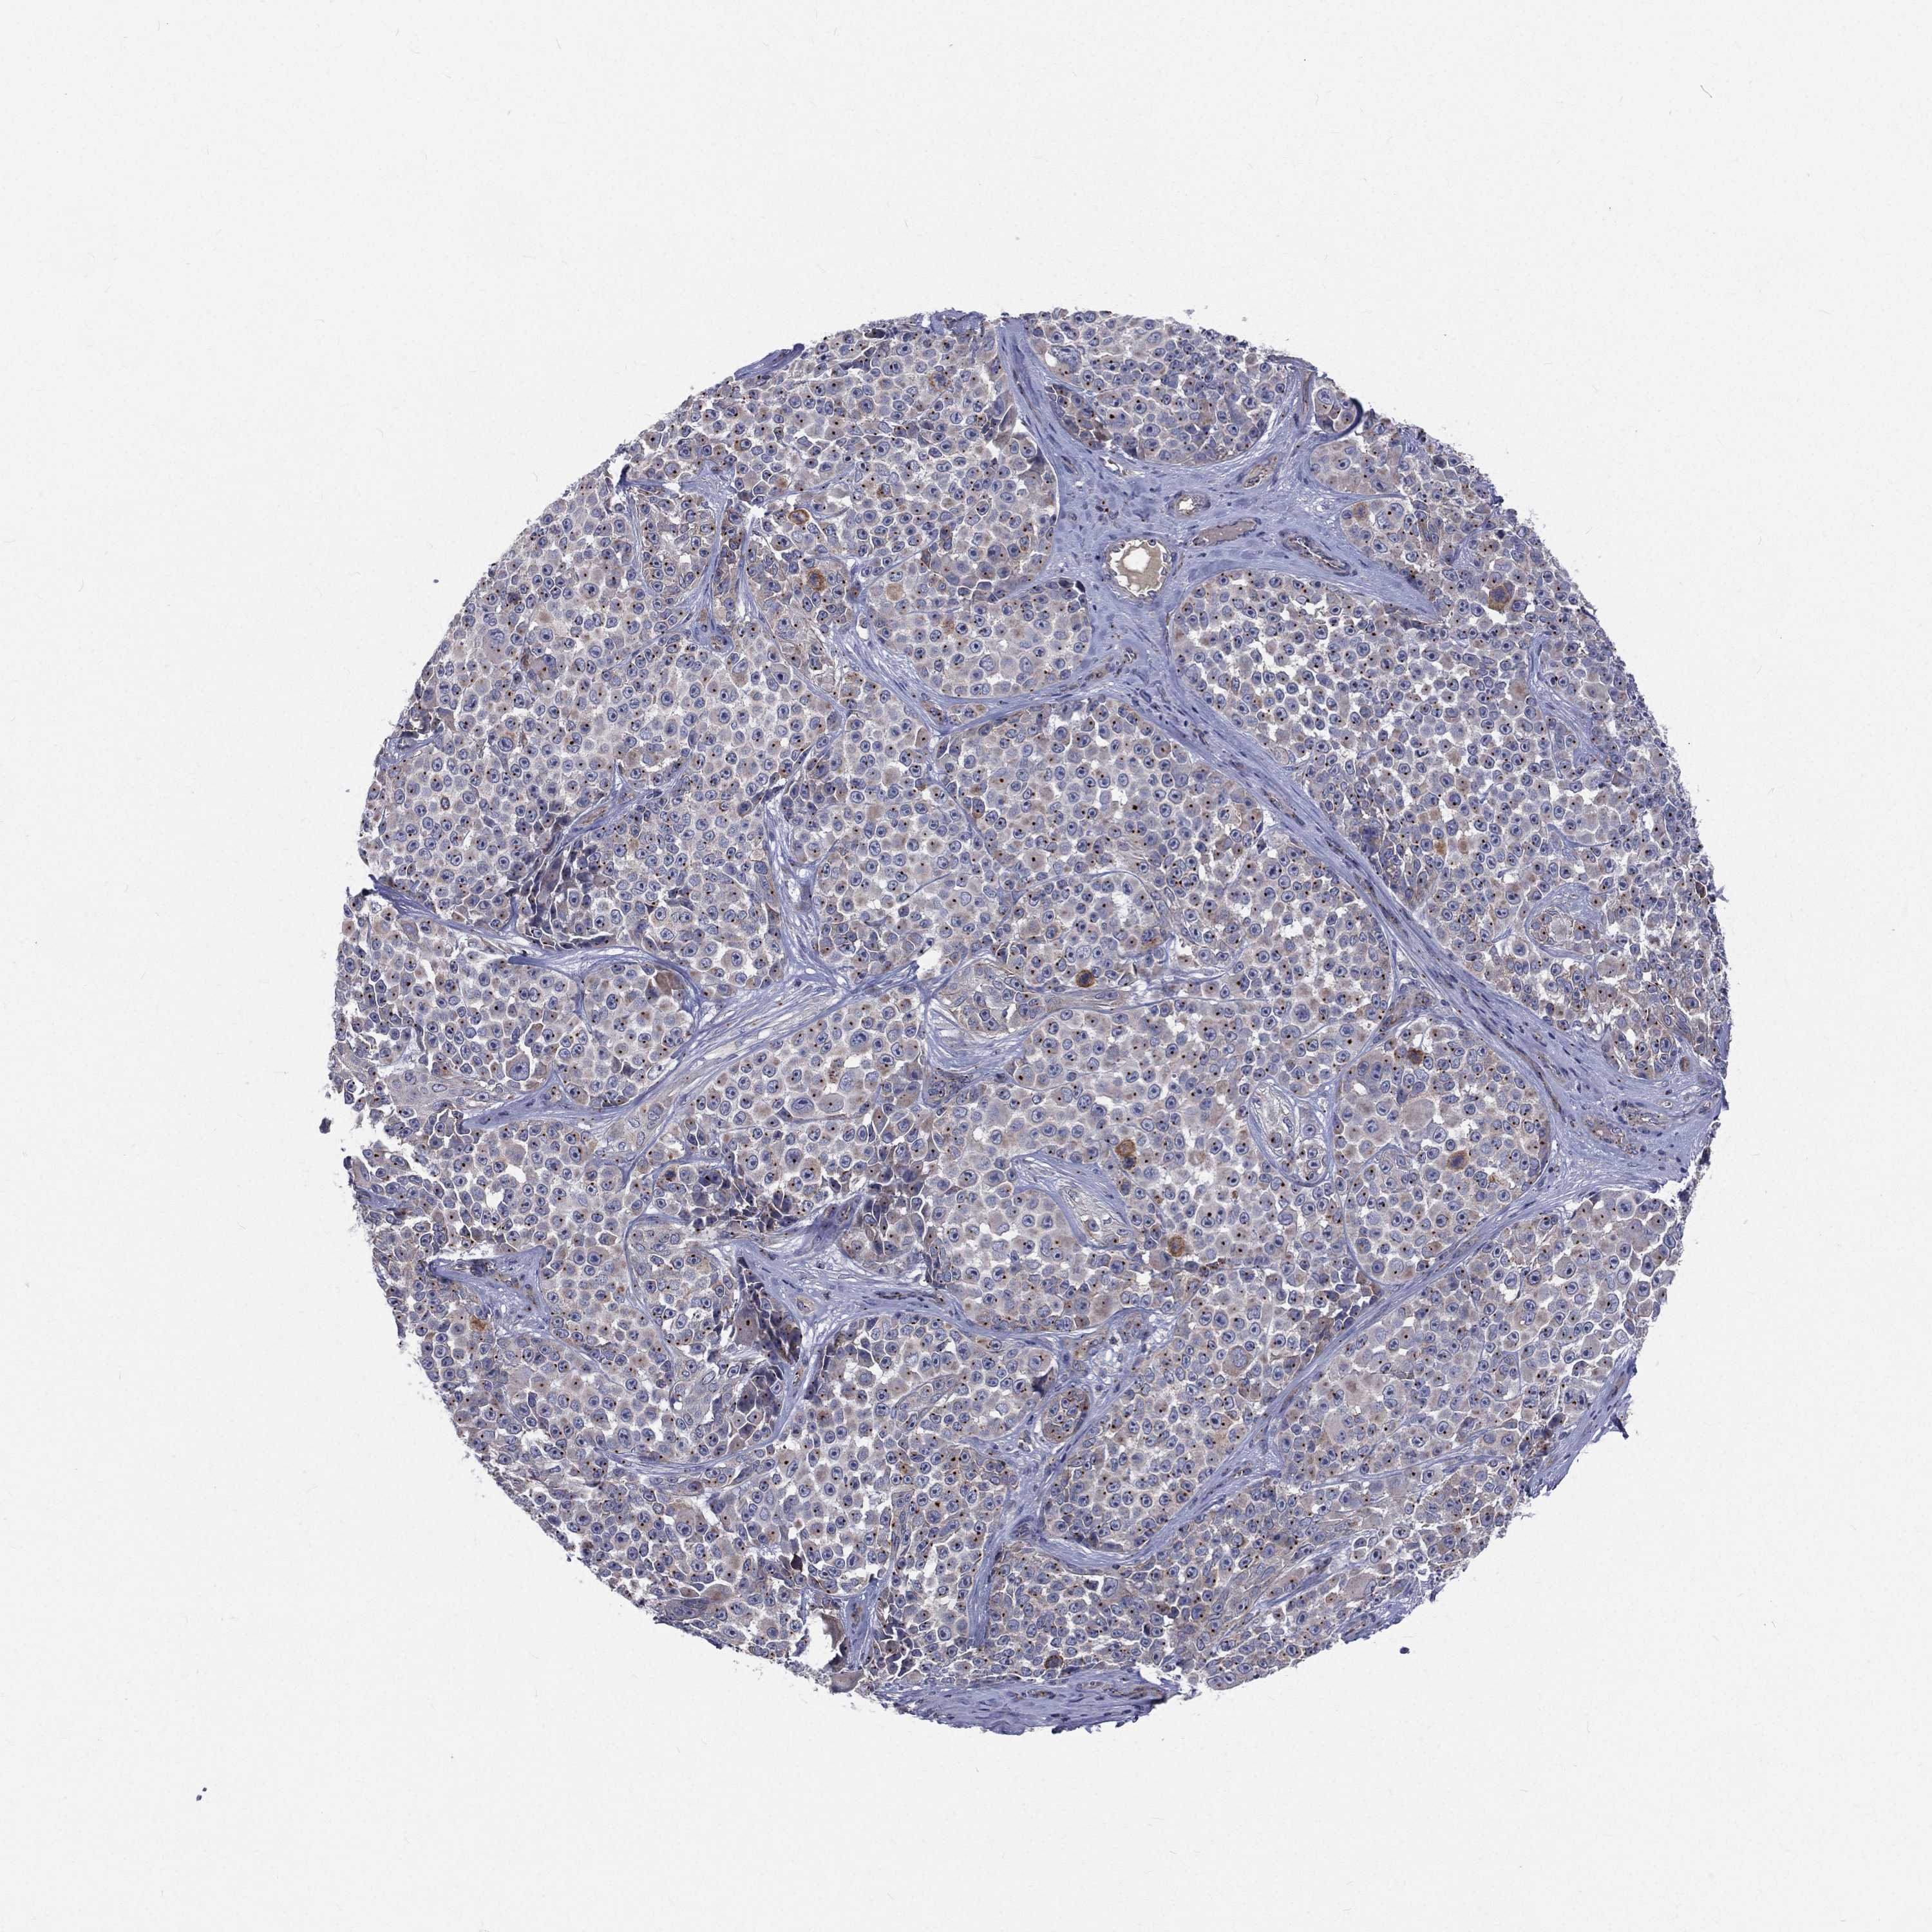

MELANOMA - Protein expressioni

A mouse-over function shows sample information and annotation data. Click on an image to view it in a full screen mode. Samples can be filtered based on level of antibody staining by selecting one or several of the following categories: high, medium, low and not detected. The assay and annotation is described here.

Note that samples used for immunohistochemistry by the Human Protein Atlas do not correspond to samples in the TCGA dataset.

Antibody stainingi

Antibody staining in the annotated cell types in the current human tissue is reported as not detected, low, medium, or high, based on conventional immunohistochemistry profiling in selected tissues. This score is based on the combination of the staining intensity and fraction of stained cells.

Each image is clickable and will lead to virtual microscopy that enables deeper exploration of all samples and also displays staining intensity scores, fraction scores and subcellular localization as well as patient and tissue information for each sample.

Antibody HPA021191

Antibody HPA021762

Malignant melanoma, NOS

Malignant melanoma, Metastatic site